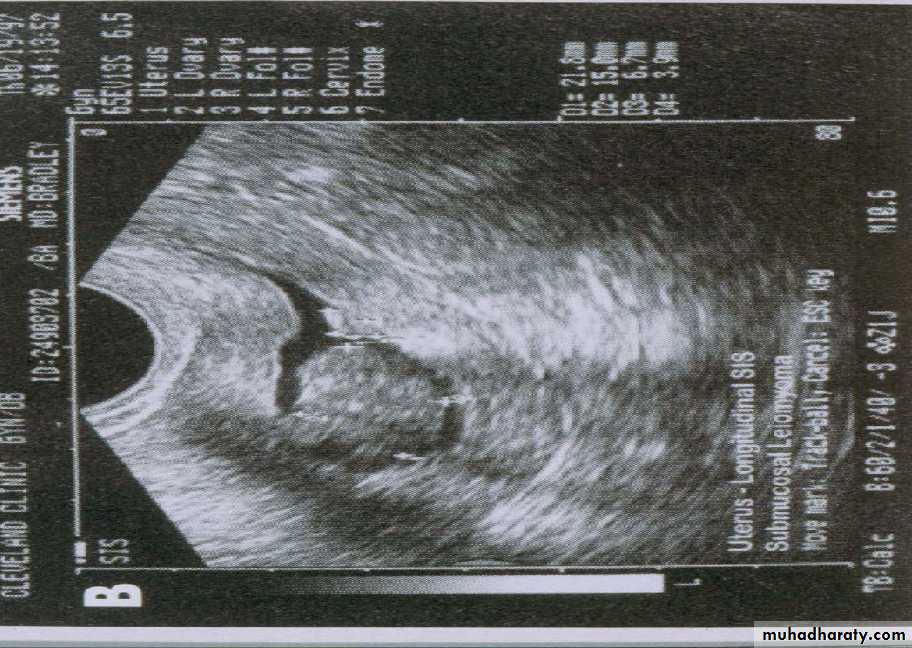

A refinement of vaginal probe ultrasound is saline infusion sonography (SIS). A salt water (saline) solution is injected into the uterus with a small tube (catheter) before the vaginal probe is inserted. The presence of liquid in the uterus helps make any structural abnormalities more distinct. These two non-invasive procedures cause less discomfort than endometrial biopsies and D & Cs, but D & C still remains the definitive test for diagnosing uterine cancer.TVUS